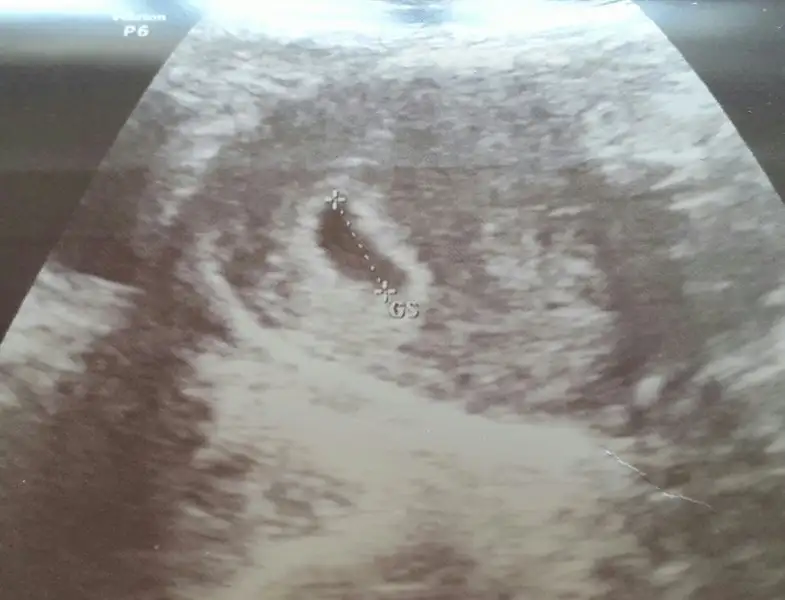

Maşallah hayırlısıyla kalp atışlarını da duyarsınız haftaya gerçekten çok heyecanlı bir süreçMerhaba arkadaşlar nasılsınız bugün kontrolüm vardı kesemiz büyümüş 1 hafta sonra kalp atışlarini dinlemek için cagardi 6+2 yiz Sata göre herkese hayırlı gebelikteler

Canım benim inşallah kötü bişey olmaz bebişin kalır seninle. Gönlünü ferah tut stres etkilemesin bebişi. Birdenmi başladı kanama nasıl oldu önceden de olmuş muydu bu şekildeKizlar dunden beri az az kanamam vardi dr a gittim düşük riski varmışkalp atisimizi duyduk çok şükür 6+5 dedi kalbi öyle guzel atiyodu ki icim gitti

Ne güzel canım resim de öyle güzel net çıkmış kiMerhaba arkadaşlar nasılsınız bugün kontrolüm vardı kesemiz büyümüş 1 hafta sonra kalp atışlarini dinlemek için cagardi 6+2 yiz Sata göre herkese hayırlı gebelikteler

Evet canım bende günleri tek tek saydim ama bu sıkıntılı süreç hiç bitmiycek kese bebek kalp atışı derken testler filan rahat olmak gerekiyo bebeği etkiliyoruz yoksa senin ne zaman kontrol canımNe güzel canım resim de öyle güzel net çıkmış ki. Ben daha kese görmedim ama beklemek çok zor ya. Günler hiç geçmiyo